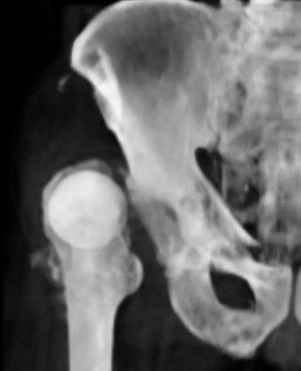

Уважаемые коллеги,Мужчина 1952 г.р. поступил в 36 больницу Екатеринбурга 1 июня 2004 г. Диагноз: Множественный перелом ребер слева, субтотальный гемоторакс, оскольчатый перелом шейки правого бедра.Повреждение таза не диагностировано. 17 июня 2004 г. - открытый остеосинтеза шейки бедра винтами с костной аутопластикой. Заживление раны первичное. Выписан 1 июля. 4 июля отметил укорочение конечности. При контрольном осмотре через 1 месяц после остеосинтеза - передний вывих бедра. Неправильно срастающийся перелом костей таза.Вопрос - особенности эндопртезирования тазобедренного сустава в этой ситуации?

По видимому снимки н/к сделаны в положении наружной ротации 90гр. И если даже так, то можно определить, что после выполненного остеосинтеза, шейка бедра практически отсутствует.

Даже при нормальной, не поврежденной впадине такое расположение головки относительно большого вертела обречено на вывих (теоретическое или биомеханическое обоснование можно найти в работах Рагозина А.О.).

Привет Слава! Думаю, что с протезированием проблем не будет, просто внимательно посмотри положение ножки - ее ориентацию (можно уменьшить антеторсию), похоже открытая репозиция была не совсем простая, сделай

сравнительные снимки обоих суставов в одинаковом положении и увидишь все причины вывиха. Огромный привет, рад тебя читать. ЛАФ Федорович - сотрудник